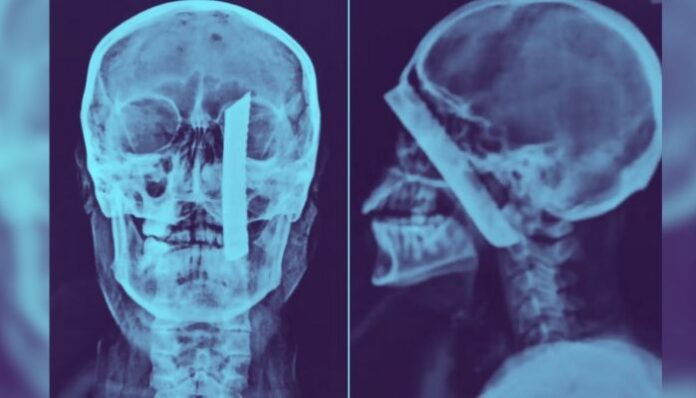

Segundo informações, a vítima teve uma lâmina cravada em sua cabeça, conforme evidenciado por imagens do exame de raios-x. O crime aconteceu em 27 de outubro do ano passado, no bairro Balneário Regina Maria.